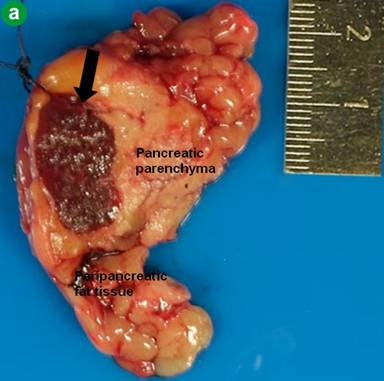

Postoperative histological examination of the resected specimen or taken biopsies revealed pancreatic metastases of extrapancreatic malignomas (Figure 1) in 8 patients (renal cell carcinoma, n=3; melanoma, n=2; duodenal gastrinoma, n=1; breast cancer, n=1; retroperitoneal liposarcoma, n=1). In 10 patients (52.6%) the following rare benign tumors were detected: solid pseudopapillary tumor of the pancreas (n=3) (Figure 2), mature teratoma of the pancreas (n=2) (Figure 3), capillary hemangioma of the pancreas (n=1) (Figure 4), intrapancreatic accessory spleen (n=1) (Figure 5), lymphoepithelial cyst of the pancreas (n=1) (Figure 6), hamartoma of the pancreas (n=1) (Figure 7), and pancreatic sarcoidosis (n=1). In one patient an advanced yolk sac tumor of the pancreas with peritoneal carcinosis was diagnosed (Table 2).

Figure 5. Intrapancreatic accessory spleen (arrow). a. Macroscopic photograph. b. Histology of an accessory intrapancreatic spleen with red and white pulpa (arrow) with a fibrous capsule next to normal pancreatic tissue (H&E-staining). |